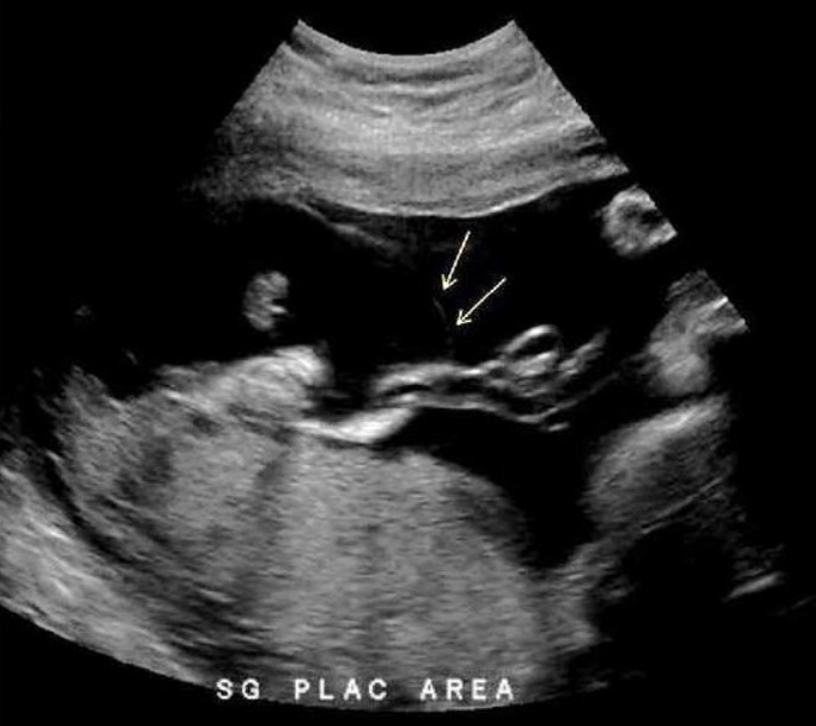

chorioangioma is supected. which image shows it

a) A

b) B

c) C

d) D